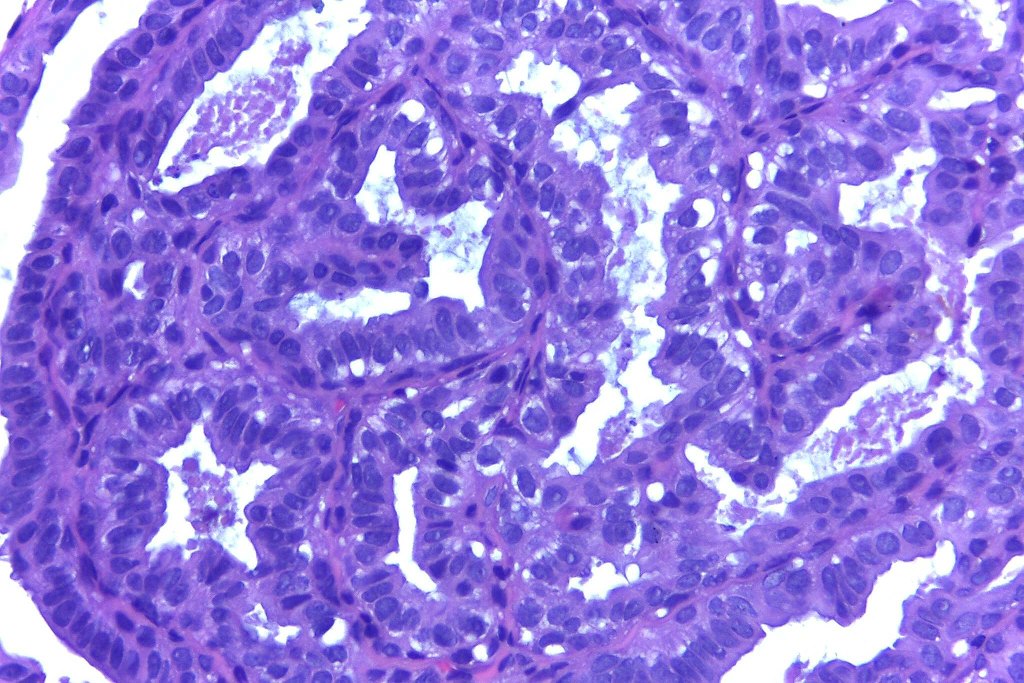

•Papillae lined by myoepithelial cells with overlying epithelial cells with eosinophilic cytoplasm showing decapitation secretion

•+/- Oxyphil metaplasia

•No pleomorphism or abnormal mitoses